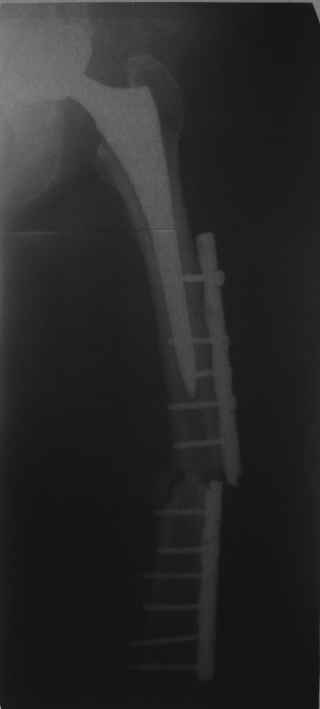

Re: Перипротезный перелом

послал SUNSINI 06 Ноябрь 2010, 05:06

Обещанные ранее снимки Заранее спасибо.